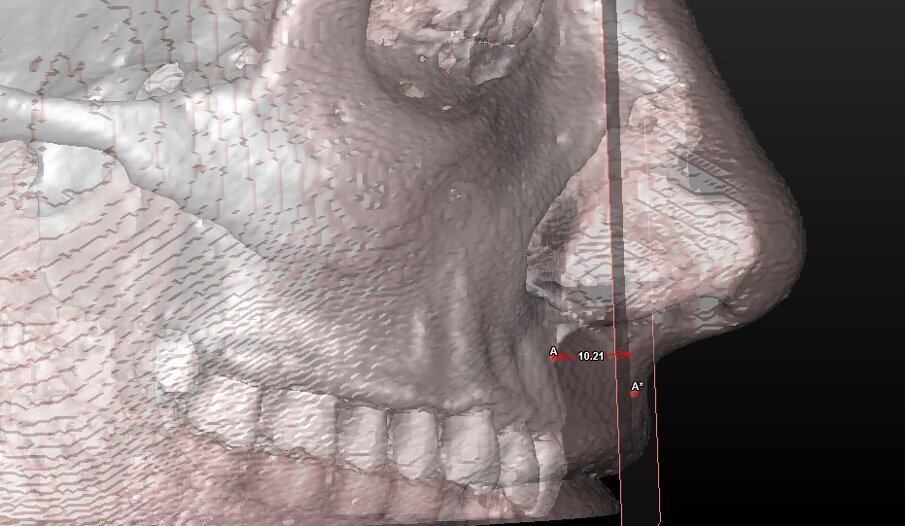

5 landmark per la valutazione estetica dei tessuti molli (Tab. 2) (Fig. 4).

| Ls (Labiale superiore) |

Punto mediano più sporgente anteriormente del vermiglio labiale superiore. |

| BLs (Bordo posteriore del labbro superiore ) |

Punto postero-inferiore del labbro superiore a livello del margine incisale. |

| A* |

Punto cutaneo del corrispondente punto subspinale A. |

Componente tessuto molle (Tab. 5) (Figg. 10a-11):

Angolo tra i punti Columella-Subnasale-Labiale superiore |

| Altezza Labbro |

mm |

19-22 |

Distanza tra il punto Sn e Ls |

| Spessore Labbro Coronale |

U13,4-16,2

D10,8-14,4 |

Distanza tra BLs e il ULp |

| Spessore Labbro Apicale |

14-16 |

Distanza tra A e il A*p |

Fig. 10b_Valutazione dei tessuti molli: altezza del labbro superiore.